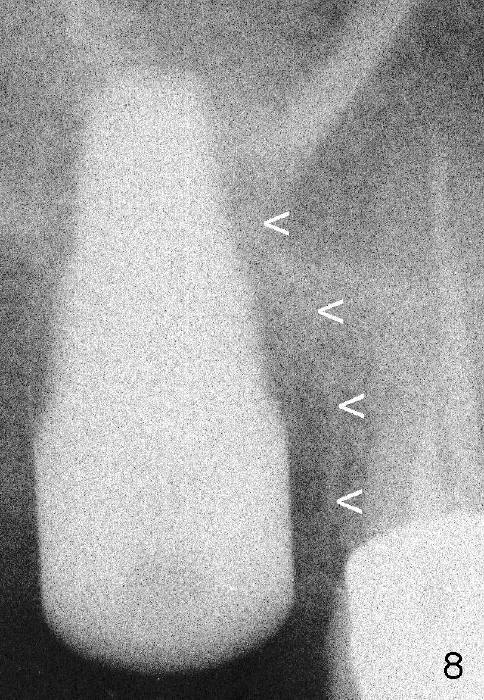

Fig.3 (preop PA) <: mesial lamina dura of the mesiobuccal root of the upper right 2nd molar.